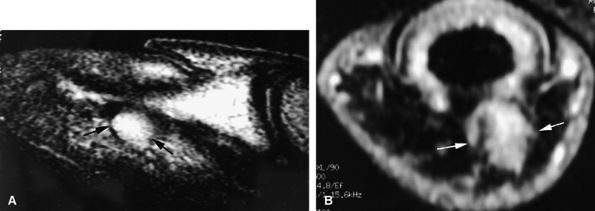

FIGURE 11.43 ● Acute open injury of the flexor pollicis longus tendon. (A) On these coronal post-contrast fat-suppressed T1-weighted images, the distal end of the tendon can be seen at the entry of the digital canal (arrows). (B) The proximal end is seen at the level of the radiocarpal joint (arrows). The tendon gap measures 6 cm. The empty tendon sheath shows significant synovitis (arrowheads in both images).

FIGURE 11.44 ● Acute rupture of the flexor digitorum profundus (FDP) tendon of the little finger in zone II. Coronal (A) and axial (B) post-contrast fat-suppressed T1-weighted images show retraction of a flexible proximal end (arrows) wrapping around the FDS tendon (asterisk).